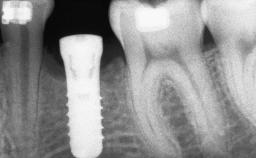

Ridge Preservation and Implant Placement for a Fixed Dental Prosthesis After a Car Accident

It is well known to clinicians that any removal of teeth will, over time, cause the dimensions of the alveolar ridge to be reduced by resorption of the bundle bone and by changes related to external modeling. This development is particularly evident in the crestal region with its thin buccal bone that consists of bundle bone almost entirely. The facial bone will rapidly resorb as blood supply from the periodontal ligament gets disrupted (Araújo and Lindhe 2005). There is no reason why traumatic tooth loss should not have the same consequences. It takes more than achieving implant osseointegration for a treatment outcome to be considered successful. No deficiency of bone or soft tissue is acceptable when an ideal esthetic outcome is the goal. Several articles (Sanz and coworkers 2011; Vignoletti and coworkers 2011) have reported on techniques of improving the alveolar ridge for implant treatment, notably focusing on protecting tissues from resorption.

# of Implants 4

Type of Implants One-Piece|Reduced-Diameter

Placement Protocol Early or late implant placement

Bone Volume Deficient vertically or deficient vertically AND horizontally